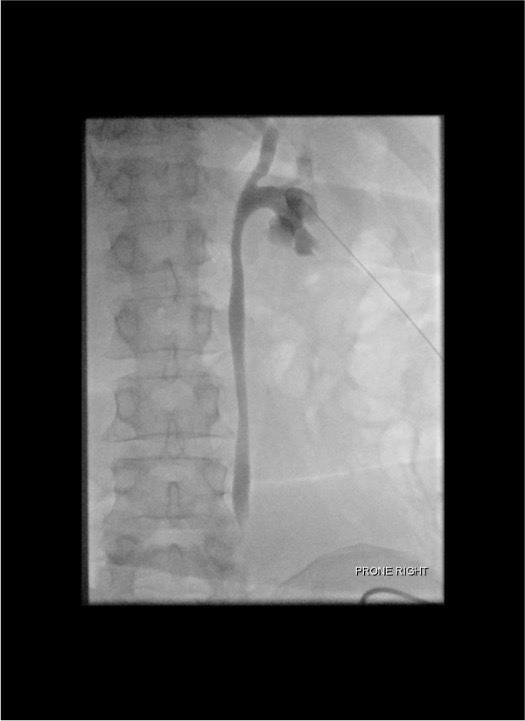

- 2Inject contrast: Slowly inject diluted iodinated contrast (1:1 with saline) through the first needle to opacify the collecting system under fluoroscopy. The pelvicalyceal anatomy is now visible.

- 3Identify target calyx: Under fluoroscopy, identify the posterior lower or middle pole calyx — look for the "end-on" calyx (appears as a circle, not a projection).

- 4Second stick — working needle: Under fluoroscopic guidance, advance an 18G or 21G access needle directly into the target calyx. The contrast outline makes targeting precise.

- 5Confirm access: Urine return or contrast aspiration from the working needle confirms calyceal entry. Proceed with standard wire and sheath placement.